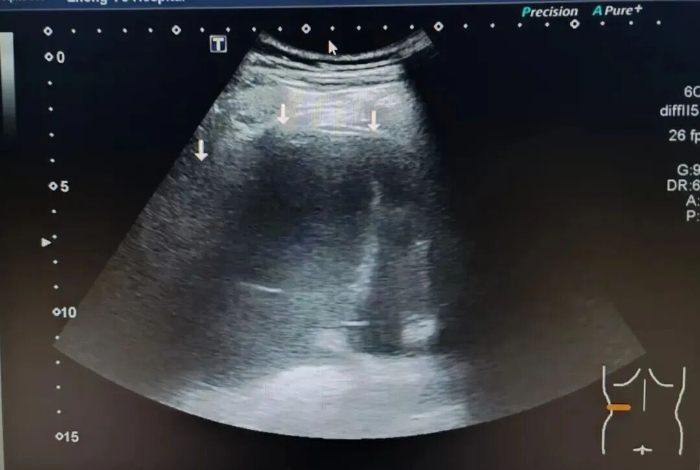

肺不张: 准确地找到那些“瘪”下去、没有气体的肺组织。

胸腔积液: 哪怕是非常少量的积液,超声也能敏锐地发现,并能协助定位,引导穿刺抽液 。